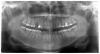

fruct Опубликовано 15 октября, 2010 Поделиться Опубликовано 15 октября, 2010 Доброго времени суток! Очень нужна консультация профи по вопросу имплантации.Предыстория такая. Был зуб (верхняя 5ка), на котором стояла коронка. В конце концов вся эта конструкция выпала, оставив в десне корни. Корни удалили, но видимо неудачно, т.к. откололся кусочек кости (на снимке его хорошо видно). Сегодня была в клинике и врач с уверенностью сказал, что нужно удалять и соседнюю здоровую 4ку, т.к. поставить имплант в текущих условиях сложно, если вообще возможно. Мне жалко удалять без показаний по сути здоровый зуб. Врач предлагает соответственно ставить 2 импланта на место 4ки и 5ки.Пожалуйста, подскажите, действительно ли есть необходимость в удалении или все-таки можно сформировать кость на месте отсутствующей 5ки и удачно поставить имплант? Примерно какова вероятность благоприятного исхода?Очень жду комментариев! Ссылка на комментарий

Surger2 Опубликовано 15 октября, 2010 Поделиться Опубликовано 15 октября, 2010 (изменено) Доброго времени суток! Очень нужна консультация профи по вопросу имплантации.Предыстория такая. Был зуб (верхняя 5ка), на котором стояла коронка. В конце концов вся эта конструкция выпала, оставив в десне корни. Корни удалили, но видимо неудачно, т.к. откололся кусочек кости (на снимке его хорошо видно). Сегодня была в клинике и врач с уверенностью сказал, что нужно удалять и соседнюю здоровую 4ку, т.к. поставить имплант в текущих условиях сложно, если вообще возможно. Мне жалко удалять без показаний по сути здоровый зуб. Врач предлагает соответственно ставить 2 импланта на место 4ки и 5ки.Пожалуйста, подскажите, действительно ли есть необходимость в удалении или все-таки можно сформировать кость на месте отсутствующей 5ки и удачно поставить имплант? Примерно какова вероятность благоприятного исхода?Очень жду комментариев!Совсем 4-ка не здоровая.ЕЕ удаление необходимо для того что-бы восстановить утраченную кость на месте 5-ки, и красиво поставить шурупик=гарну короночку.В противном случае (если поставить шурупик туда куда есть + небольшая подсадка) эстетики не будет.Не плохо бы глянуть прицельный снимок. Изменено 15 октября, 2010 пользователем Surger2 Ссылка на комментарий

Bier Опубликовано 15 октября, 2010 Поделиться Опубликовано 15 октября, 2010 боюсь что ваша "здоровая" четверка - вовсе не здоровая, а давно депульпированная, причем не качественно. Ваш доктор прав, ее надо удалить, без этого кость не нарастить. Ссылка на комментарий